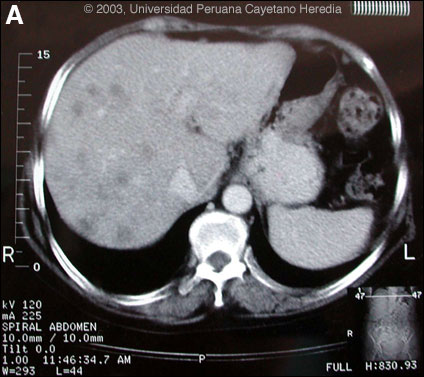

Epidemiology: Farmer from just outside Lima. Her husband, who had a history of chronic alcoholic liver disease, had become ill at the same time and died with icterus, ascites, and hypereosinophilia. Just prior to the illness the husband had heard of beneficial health effects of watercress (called berros in Perú) and she had bought a large amount of it, which was consumed on only one occasion. Physical Examination: Pale. Afebrile. Liver non-tender 3 cm below costal margin. No splenomegaly. Laboratory Examination: Hematocrit 31. WBC 15,600 with 21 neutrophils, 18, lymphs and 56 eosinophils. Blood cultures negative. Liver function not repeated. Hepatitis A, B, C, serology negative. Stool O & P and serological tests were ordered. Available CT image [Image A] is from 3 months later but is representative of findings throughout the illness.

![]() Discussion: 2 of 6 stool concentrates showed scanty eggs of Fasciola hepatica. Arc-2 immunoelectrophoresis and western blot were both positive for Fasciola hepatica. Fasciola hepatica is a trematode (fluke or flatworm) in which the adults inhabit the large biliary ducts. The adults are from 1 to 3 cm long and attach to the biliary epithelium by a single ventral sucker [see Images B, C from our files for endoscopic view of an adult in the common bile duct]. In the absence of direct visualization, characteristic eggs can be seen on stool examination but more often, especially in the early migratory phases of infection, as should have been done at the referring hospital, specific serology must be obtained. As with all other trematodes, Fasciola hepatica requires a snail intermediate host. Eggs produced by the hermaphroditic adults pass with the feces and hatch, releasing larvae in fresh water. After passing through a snail, mature cercariae emerge and rapidly encyst on various kinds of aquatic vegetation such as watercress. After ingestion by a human or animal definitive host, the metacercariae excyst in the duodenum and larvae pentetrate the intestinal wall and subsequently migrate directly into the liver via Glisson's capsule. The larvae then migrate through the hepatic parenchyma for 3 to 4 months until they reach large biliary ducts where they mature to adults. The distribution of Fasciola hepatica is cosmopolitan, but is by far the most common in sheep-raising areas where these herbivores are common definitive hosts. Heavily infected sheep develop "sheep liver rot". Other important definitive hosts are goats, cattle, horses, llamas, vicunas, and camels. The contiguous altiplano regions of the Peruvian and Bolivian Andes are highly endemic, with human prevalence rates of as high as 67% in some villages. Egypt, Cuba, and Northern Iran are also highly endemic. Cooking, which would kill the metacercariae, dramatically changes the flavor of watercress and the population is reluctant to adopt this simple measure. Clinically, the disease can be divided into acute and chronic phases. In the acute phase, migrating larvae cause inflammation and necrosis of hepatic parenchyma during the 3 to 4 months it takes to reach the large biliary ducts. High fever, eosinophilia, right upper quadrant pain and especially significant anorexia, vomiting and weight loss of 20 kg or more may develop, which usually abates when the larvae mature to adults. The adult flukes in the biliary tree are generally asymptomatic but some patients develop chronic manifestations including right upper quadrant pain, nausea, vomiting, and hepatomegaly. Eosinophilia and abnormal liver function may develop but are less common than with acute disease. Adult flukes may cause hyperplasia, desquamation, thickening, and dilatation of the bile ducts. Malignant degeneration and cholangiocarcinoma such as results from chronic infection with the oriental liver fluke Clonorchis sinensis has not been reported with Fasciola hepatica. The differential diagnosis of hypereosinophilia with accompanying destructive hepatic lesions is limited. Toxocariasis causes hypereosinophilia with hepatomegaly but the pathology results from small granulomas around individual non-migrating larvae and not the large destructive tracks as was seen on the CT in our patient. Only case reports but no series of sequential CT scans of the acute phase of fascioliasis have been published. Lesions are irregular, hypodense, sometimes oblong and branching. One recent published case shows serial CT scans over a 9-month period demonstrating changes in position, and shape of lesions over time, as would be consistent with the destructive nature of the migrating flukes [N Engl J Med. 2002 Apr 18;346(16):1232-9]. Fasciola hepatica is the only trematode infection for which praziquantel is not the drug of choice. WHO has put the veterinary anthelmintic triclabendazole (Novartis) on its essential drugs list and has declared it the drug of choice despite the fact that human preparations are registered in only 2 countries. In Perú, the veterinary preparation is readily available and used. In the U.S. and many other countries the veterinary preparation can be obtained by special release from the manufacturer. The usual dosage is 10 mg/kg with a meal. Many practitioners repeat the dosage 12 to 24 hours later. In our institute the cure rate is 96% (A. Terashima, unpublished). Our patient was treated with a single 2-day cycle of triclabendazole with symptomatic improvement and a weight gain of 10 kg. Eight subsequent stool examinations were negative. Three months after treatment, the patient required hysterectomy for uterine fibromas and liver biopsy performed at that time due to the persistent CT abnormalities showed residual microabscesses with PMN infiltration, fibrotic granulomatous reaction but no parasites or eosinophilic infiltrate. Peripheral absolute eosinophil count at that time was 780. A final CT examination 6 weeks post-operatively [not shown] now shows significant reduction in the number of lesions. The earlier case report [N Engl J Med. 2002 Apr 18;346(16):1232-9] had followed sequential lesions over 9 months prior to any treatment. We demonstrate that in a case of massive fascioliasis such as here, the destructive inflammatory tracks made by migrating larvae persist radiologically and histologically for months even after apparent parasitic cure. In addition, the patient’s husband, due to his underlying chronic liver disease, almost certainly died of massive fasciola infection and this degreee of infection in both husband and wife was after a single exposure to contaminated watercress.